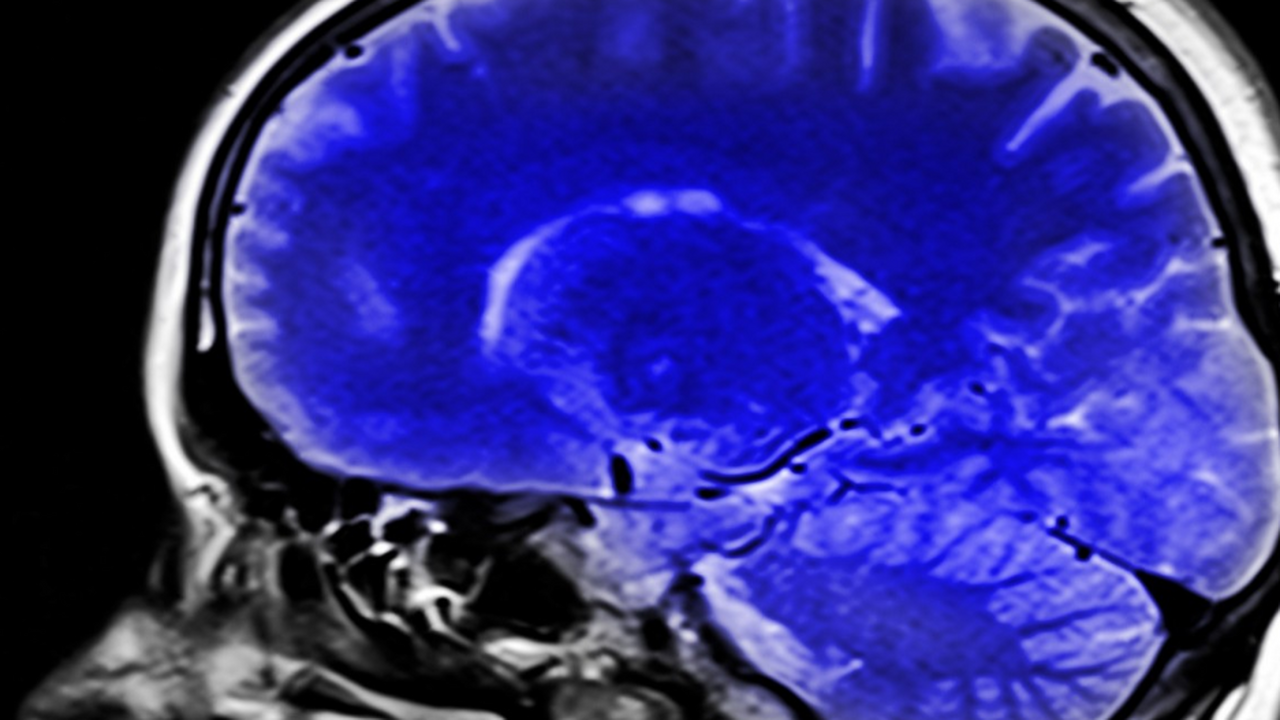

Глиобластома, один из самых агрессивных видов рака мозга, использует глюкозу не так, как здоровые клетки, что способствует её быстрому росту.

Согласно исследованию, опубликованному в журнале Nature, опухоль перенастраивает сахарный обмен и превращает глюкозу не в энергию, как это делают обычные клетки, а в строительные блоки для ДНК и РНК. Это позволяет раковым клеткам быстрее делиться и распространяться по организму.